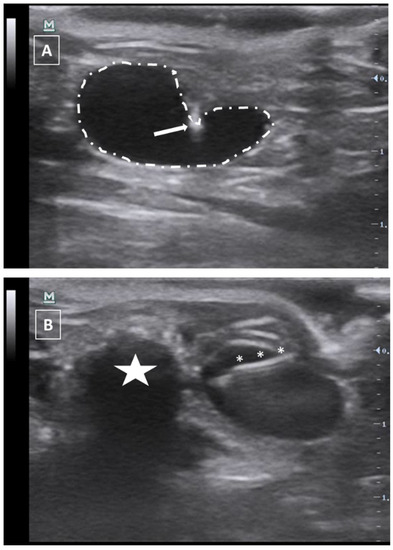

The needle can be seen inside the left ventricle as a hyperechoic linear structure with reverberation artifacts in an anechoic background. During the injection, we will be able to see some small hyperechoic dots coming from the needle. These are microbubbles created during the needle filling. These dots will confirm the correct injection in the anechoic ventricular cavity. Once the injection is completed, the needle can be removed. An example of an intracardiac injection can be seen in Figure 3.

The duration of this process depends on the expertise of the user. An experienced ultrasonographer can do the injection in less than a minute. The major risk of this procedure is the incorrect injection in the right ventricle, the lung, or the mediastinum. We will not see the hyperechoic bubbles arising inside the left ventricle. Other less frequent errors can be damaging the aorta the cava vein or any of the cardiac atriums. In these cases, we will see an acute intrathoracic hemorrhage.

Figure 3. Intracardiac injection. (A) Preinjection image. Needle is marked with white asterisks and left ventricle area is surrounded by a dashed line. Lung artifact is labeled with white arrows. (B) Injection moment. Multiple white dots (marked with white arrows) inside the left ventricle correspond to microbubbles injected with the suspension. Images obtained with 40 MHz frequency.